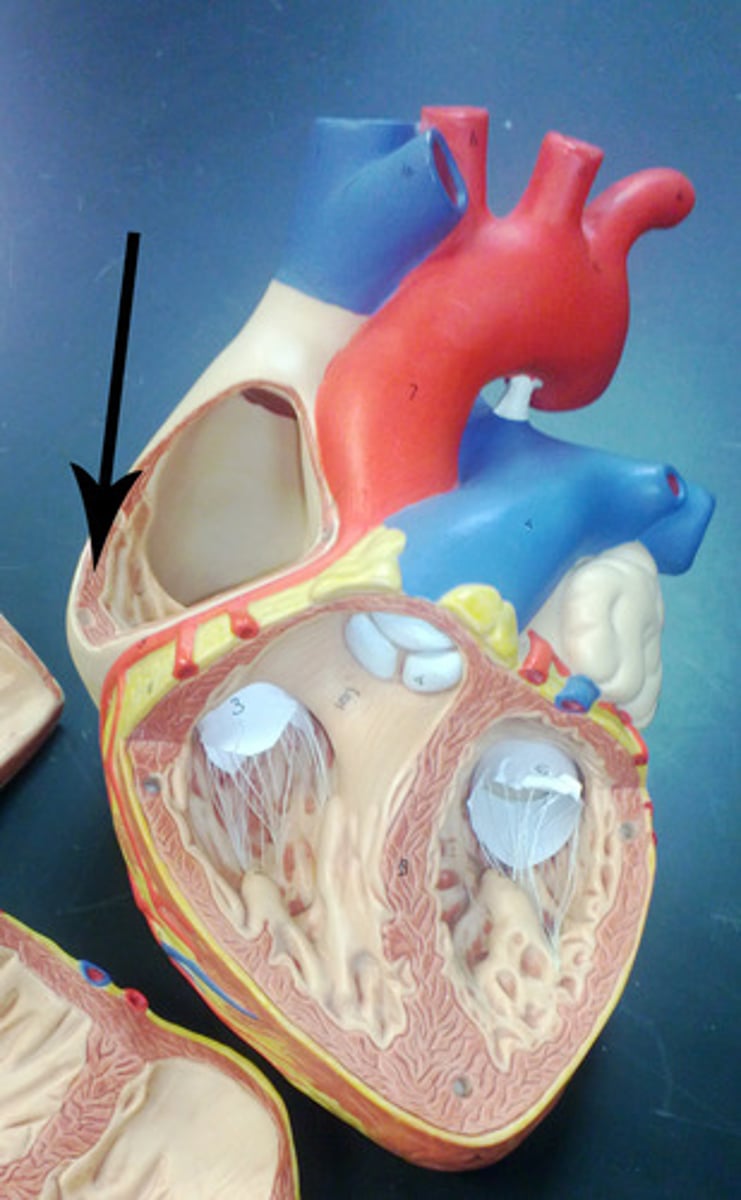

Two atria; right and left (receiving chambers)

Two ventricles; right and left (discharging chambers)

Pectinate muscles

Ridged wall of atria (contracts)

Trabeculae carneae

Ridged wall of the ventricles (contracts)

Papillary muscles

Have chordae tendineae that are attached to the valve flaps so they don't prolapse

Foramen ovale, remnant structure is fossa ovalis

During embryonic development, shunts blood from the right atrium to the left atrium to bypass the nonfunctional lungs

From: Left atrium through the bicuspid valve

To: Aorta through semilunar valve to systemic system

From: Right atrium through tricuspid valve

To: Pulmonary trunk (artery) through semilunar valve to lungs then pulmonary veins

Atrioventricular valves (tricuspid and bicuspid)

Prevents back flow into atria

Semilunar valves (aortic and pulmonary)

Prevents back flow into ventricles

Both have three flaps

Don't have papillary muscles